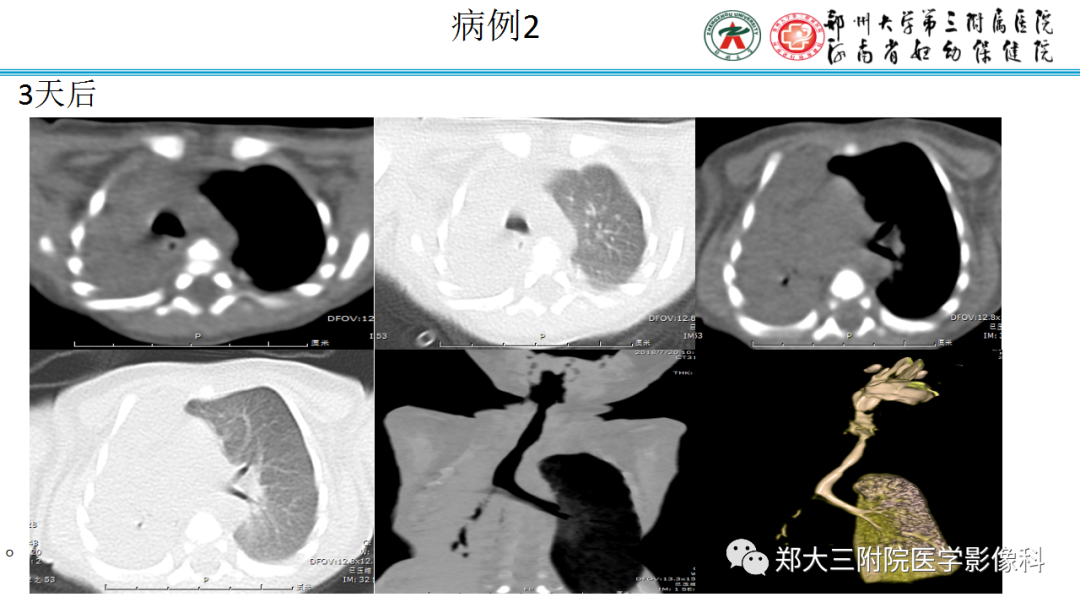

【影像表现】 钡灌肠:直肠与乙状结肠起始部可见不规则充盈缺损(图1箭头),肠管见偏心性狭窄;粘膜皱襞紊乱,纠集(图2、3箭头)。 CT:直肠壁不均匀增厚,见软组织影突入直肠腔内,增强扫描中度强化,周围脂肪间隙欠清楚,直肠后方可见肿大淋巴结(箭头)。肝脏体积增大,肝内密度欠均匀,可见多发弥漫不均匀低密度区,增强扫描病灶显示更加清楚,呈多发结节样低密度影,脾周及胆囊窝周围可见少量液性低密度影。

CT:(1)肠壁增厚,增厚的肠壁黏膜面多明显凹凸不平。(2)腔内肿块影,偏心性,呈分叶状或不规则形,与正常肠壁分界清楚,肿块表面可见小溃疡,呈火山口样。(3)肠腔狭窄,且为非对称性。(4)增强扫描可见较明显异常强化。(5)浆膜及临近器官受侵表现。